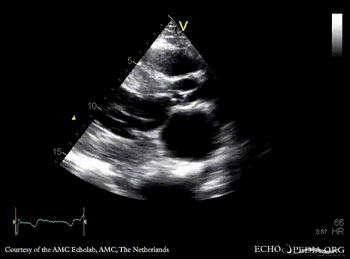

Subvalvular membrane in left ventricle outflow tract

Suprasternal view: Collor Doppler, high velocity flow in left ventricle outflow tract Continuous-wave signal of high flow in left ventricle outflow tract